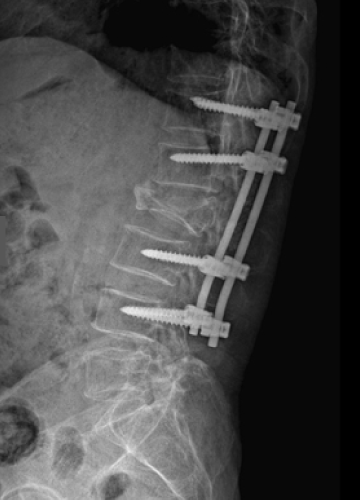

척추골절 치료법

척추 압박골절은 찌그러지고 주저앉은 척추뼈에 골시멘트를 주입시켜

그 모양을 복원시켜주는 척추체 성형술로 간단하게 치료할 수 있습니다.

단, 골절이 심하여 척추뼈가 신경을 심하게 압박하는 경우나

척추뼈의 골절이 심한 파열 골절의 경우는 수술적 치료가 필요할 수 있습니다.

수술적 치료는 척추뼈가 움직이지 않고 신경을 자극하지 않도록 하는 고정술을 주로 시행합니다.

척추 고정술 치료 방법

2020.06.09

2020.08.11

ㆍ환자 동의를 받은 자료이며, 이미지 사진은 실물과 다를 수 있습니다.

ㆍ모든 자료는 새움병원 자료입니다.